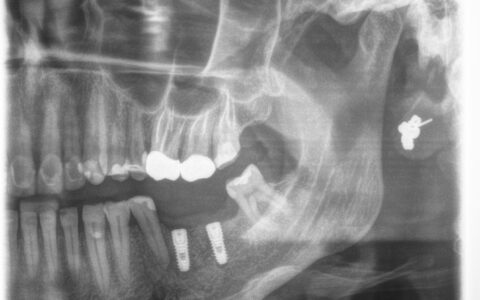

Zdjęcie RTG pacjentki przed implantacją oraz po wszczepieniu 2 implantów.